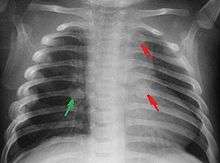

Rib fractures in an infant secondary to child abuse

The immediate physical effects of abuse or neglect can be relatively minor (bruises or cuts) or severe (broken bones, hemorrhage, or even death). In some cases the physical effects are temporary; however, the pain and suffering they cause a child should not be discounted. Rib fractures may be seen with physical abuse, and if present may increase suspicion of abuse, but are found in a small minority of children with maltreatment-related injuries.[61][62]